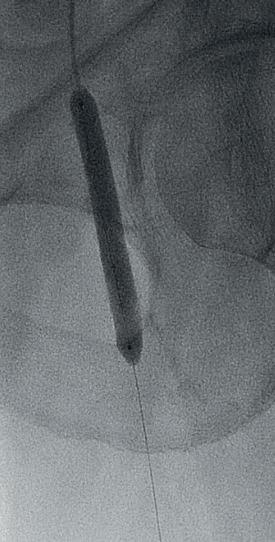

THE PATIENT IS AN 81-YEAR-OLD man with a past medical history of hypertension, hyperlipoproteinaemia, and remote history of smoking, who presents with an expanding saccular abdominal aortic aneurysm (AAA) and severe hip claudication. A preoperative computed tomography angiography (CTA) reveals dense circumferential calcified 90% stenosis of the bilateral common iliac arteries (Figures 1 and 2). In addition, the patient had a mid-aortic highly calcified stenosis. The patient desired a minimally invasive approach and given the underlying conditions, an EVAR was the best option to treat the AAA, as well as the bilateral common iliac artery stenosis.

Preoperative planning focused on three main areas of concern: the first is whether or not the stent graft could advance through the iliacs; secondly, would the stent graft limbs open to nominal diameter within the iliacs; and lastly, whether or not the stent graft would open fully within the AAA.

We used a percutaneous approach. Initially, we were unable to advance the 16Fr DrySeal sheath for the main graft on the right or the 12Fr DrySeal sheath on the left side for the contralateral limb (Figure 3). At this point, we performed IVL with a 7.0x60mm IVL catheter, of both the right and left common iliac arteries. We delivered 150 pulses to each vessel at 4atm and subsequently carefully dilated to nominal pressure of 6atm. Both arteries dilated easily. The Gore Excluder graft was delivered, and the limbs were placed within the common iliac arteries. Post-implantation balloon angioplasty was completed and revealed complete seal of the AAA and no residual stenosis in the iliacs (Figure 4). The patient was found to have a 90% stenosis of the left renal artery, which was treated with a balloon-expandable stent. His postprocedural CT scan revealed a very nice result, a sealed AAA, wide iliac arteries, and no residual stenosis.

Figure 3. Initial intraoperative angiogram

Figure 1. Preoperative CTA revealing dense calcified stenosis of the iliac bifurcation

Figure 4. Completion arteriogram, areas of stenosis completely resolved

common iliac luminal diameter of 3mm, left common iliac diameter of 5mm